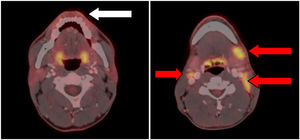

Una tomografía computarizada con emisión de positrones (PET-TC) mostró una lesión hipermetabólica focal en el labio inferior izquierdo, con relación al proceso tumoral primario con afectación adenopática múltiple laterocervical bilateral y supraclavicular izquierda. Sin otras lesiones hipermetabólicas patológicas (fig. 2).